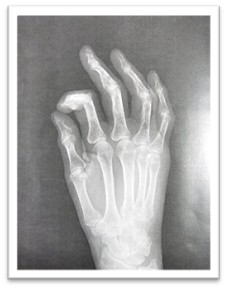

- Hoy os traemos el caso de una paciente mujer de 72 años que el día 21-01-2024 sufre una caída y se golpea en la mano derecha.